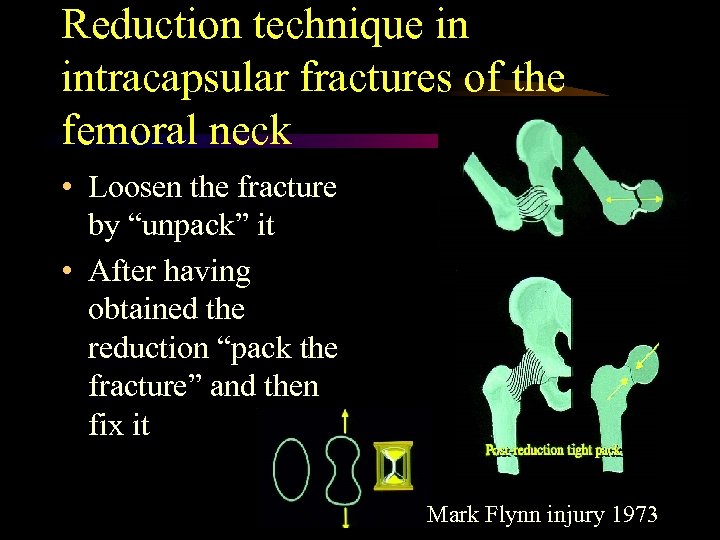

Reduction technique in intracapsular fractures of the femoral neck • Loosen the fracture by “unpack” it • After having obtained the reduction “pack the fracture” and then fix it Mark Flynn injury 1973

Reduction technique in intracapsular fractures of the femoral neck • Loosen the fracture by “unpack” it • After having obtained the reduction “pack the fracture” and then fix it Mark Flynn injury 1973